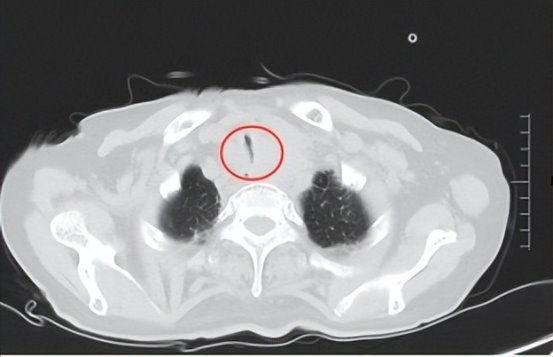

经详细检查,患者食管恶性肿瘤生长迅速,导致外压性气管狭窄程度超过95%,仅剩极窄的缝隙用于通气。患者出现了进行性呼吸困难,无法平卧,意识也逐渐模糊,濒临窒息。传统的气管插管无法通过如此狭窄的管腔,而开胸手术风险极高,患者身体状况难以承受。在仅2 - 3毫米的狭窄空间内进行操作,既要防止肿瘤破裂出血,又要维持患者的氧合,这对手术团队的技术和经验是极大的考验。

手术使用硬质气管镜快速建立生命通道,为后续操作创造了必要的空间。超细支气管镜深入狭窄段,准确定位支架释放区域。将镍钛合金网状支架精准展开,瞬间撑开了“塌陷隧道”,恢复了气道的通畅。

(术前气管镜检查)